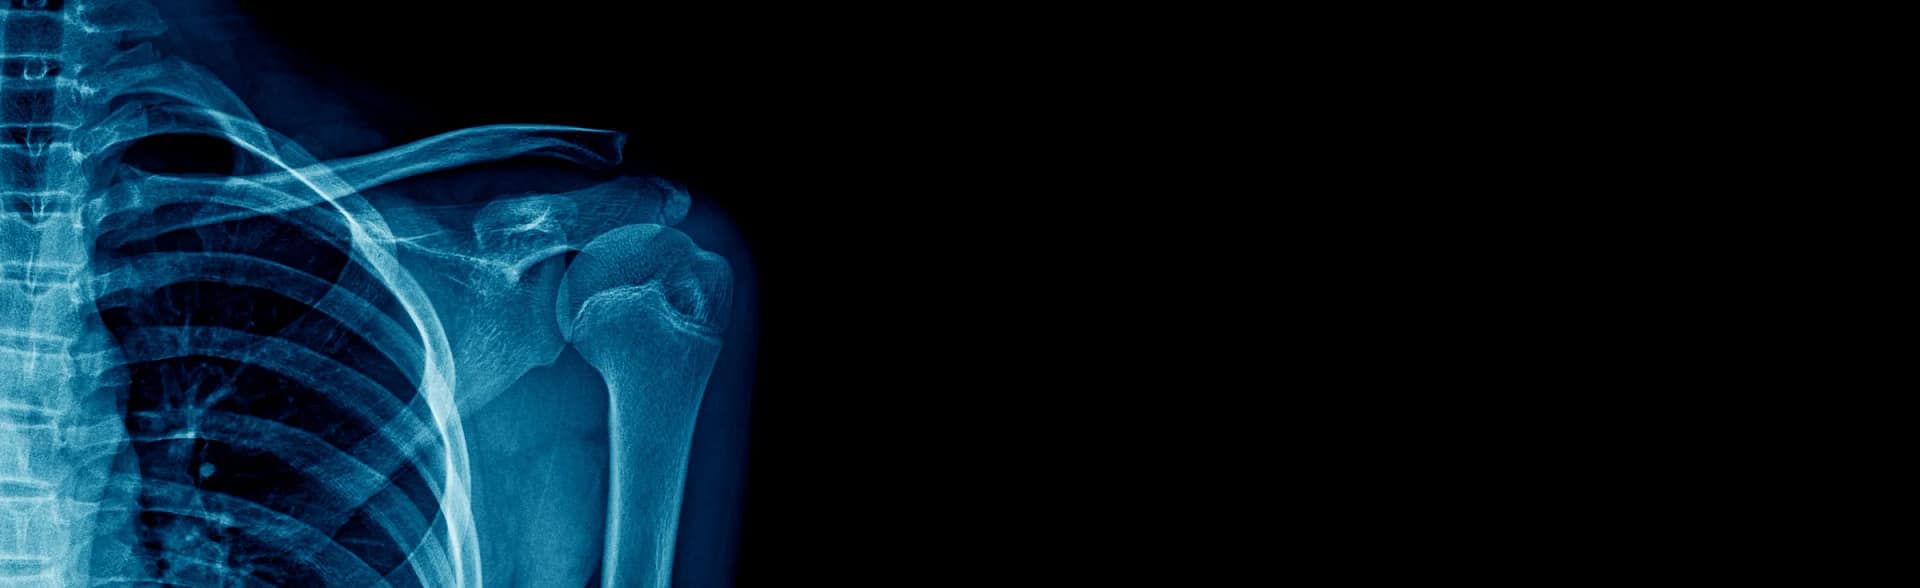

Shoulder X-ray and CT imaging in selected cases can be useful to exclude other potential injuries and to further assess the fracture, particularly in cases where surgical management is required. The investigations will help to inform the clinician regarding treatment plans.